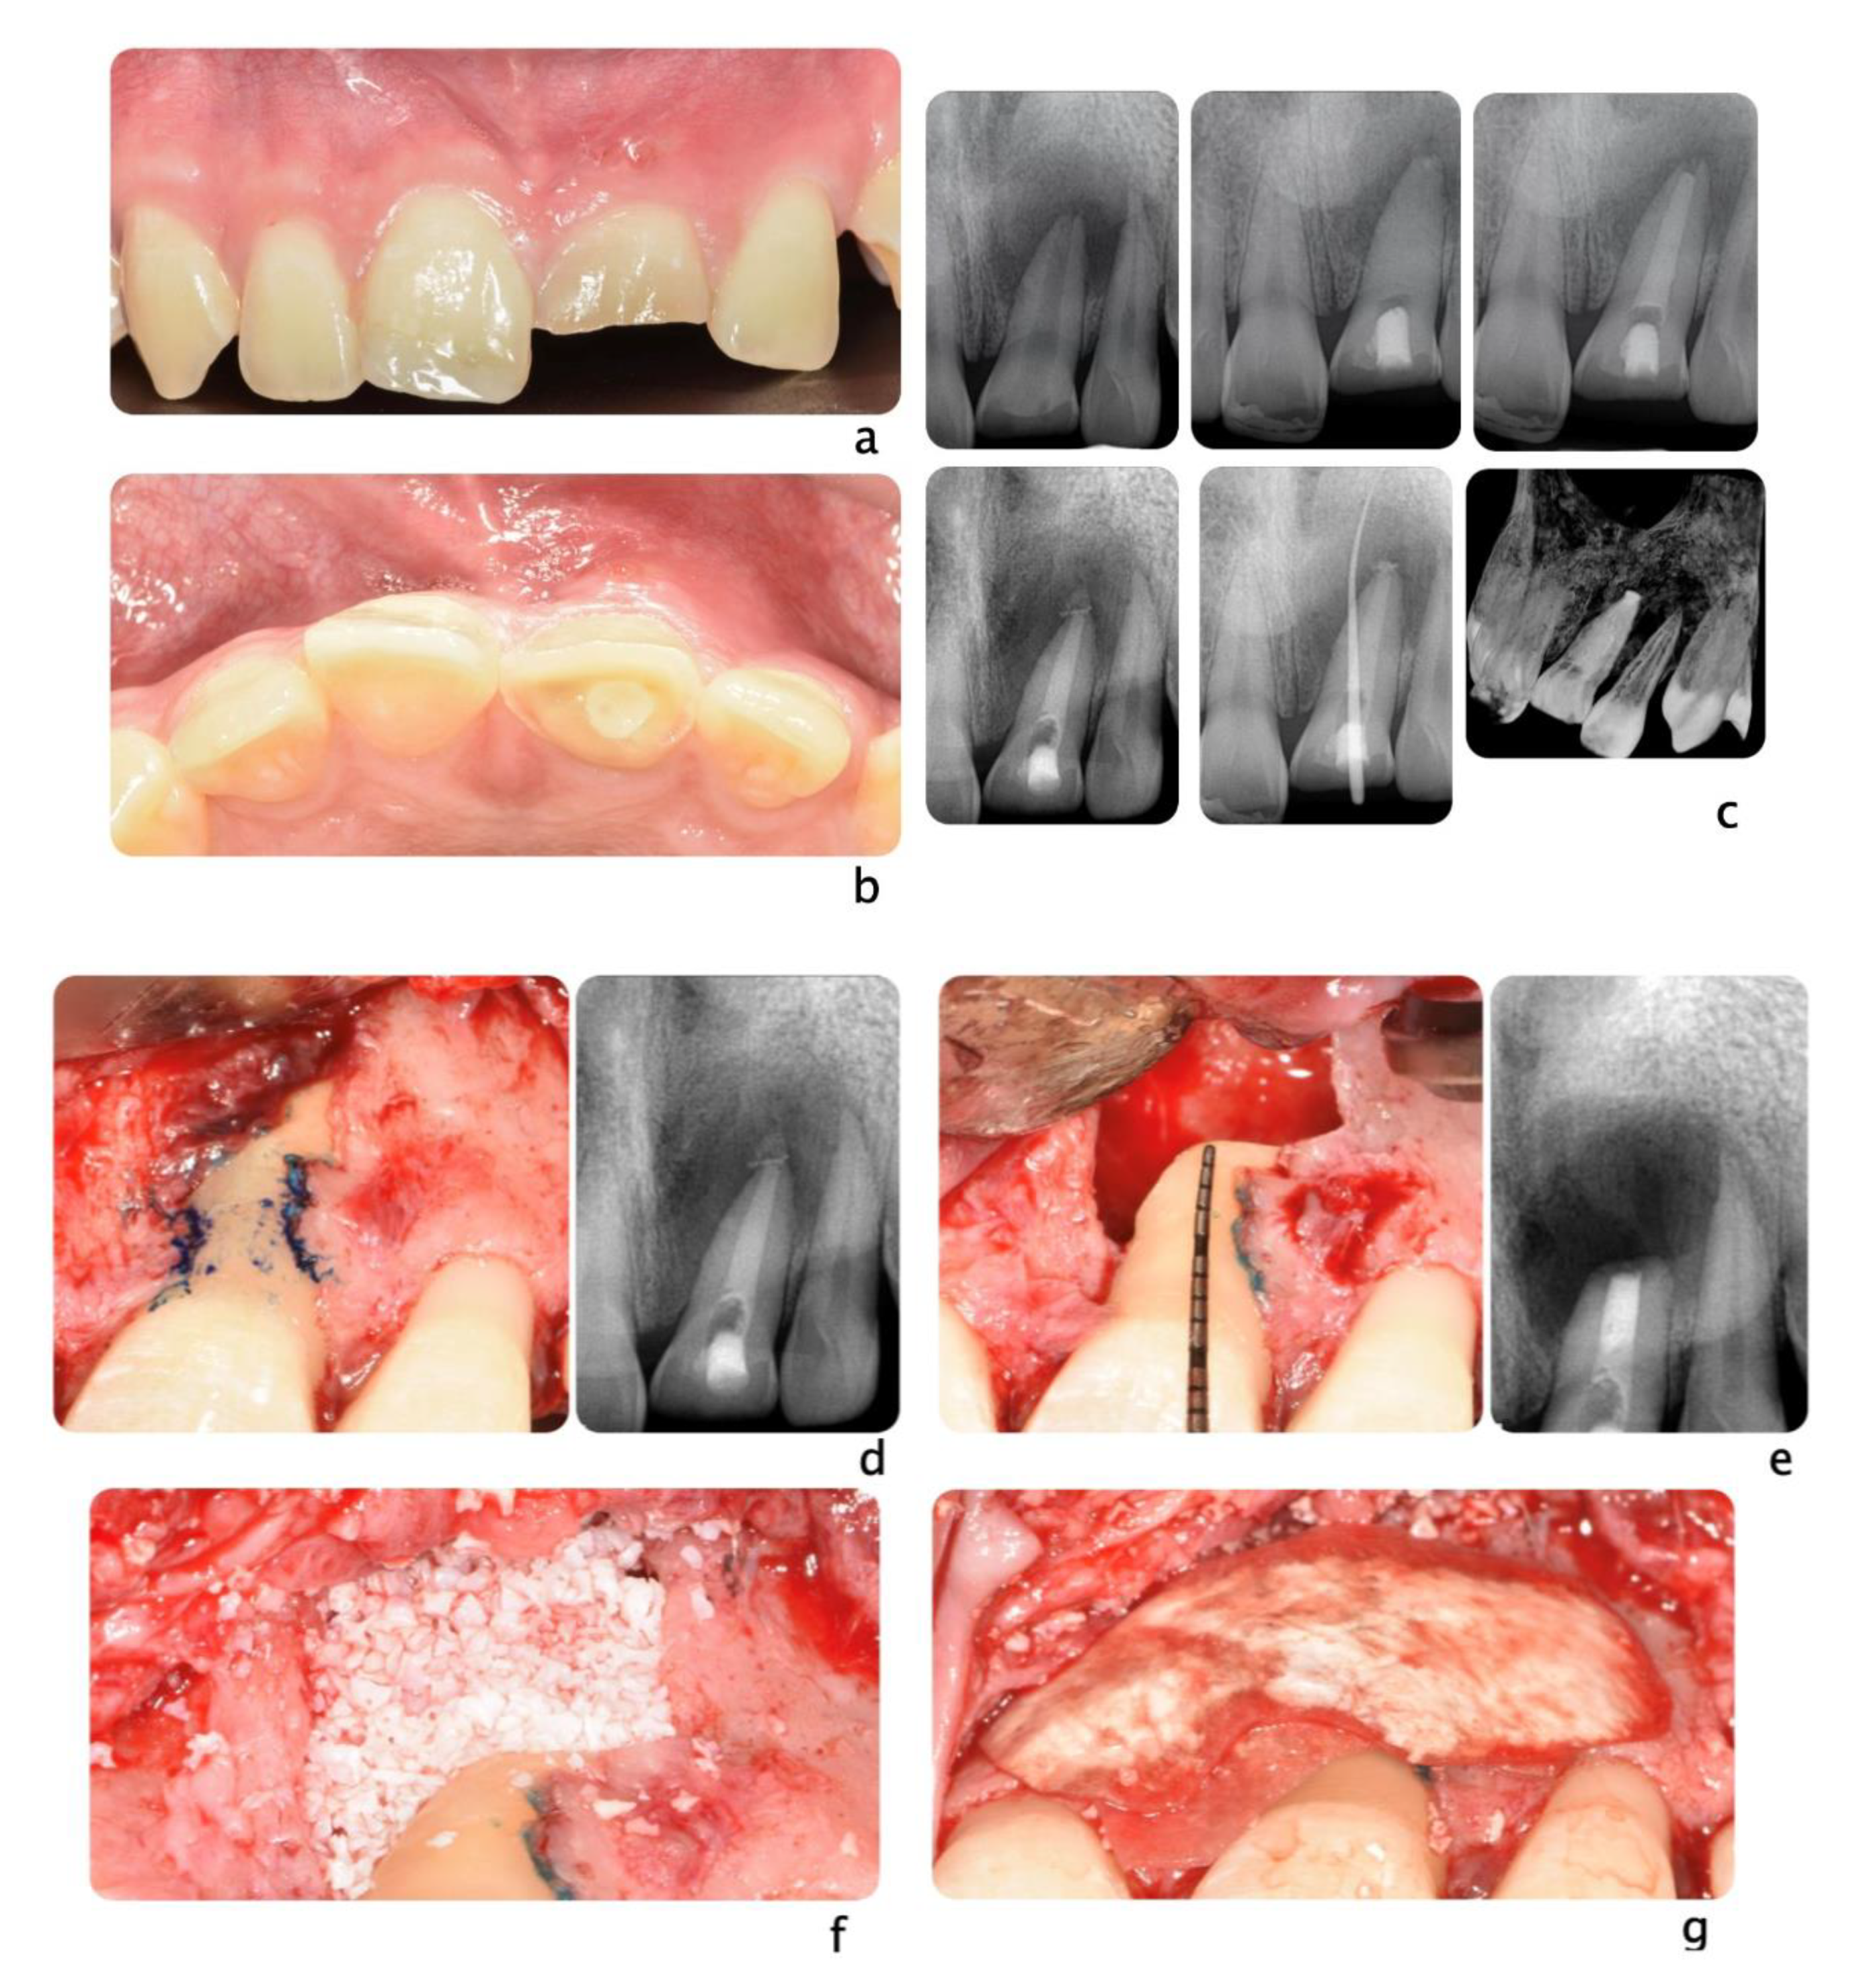

Figure 5.

Clinical scenario of a 17 years-old adolescent hit by a baseball ball in the anterior maxillary region. The boy presented to the Periodontal Department at Tufts University, Boston USA with crown fracture of left central incisor (#9) (a,b). Peri-apical radiograph show apical radiolucency, sign of necrosis. After the diagnosis, CaOH2 was applied. The root canal definitive treatment was completed but after 2 months the patient still presented with a fistula, that was tracked via a gutta-percha point. A CBCT scan was performed in order to diagnose the extent of the peri-apical lesion (c in sequence). The extent of the lesion did not suggest an endodontic therapy revision. Exploratory surgery was performed in order to rule out tooth fracture (d). The apex was resected in order to access the palatal aspect of the tooth. A PA radiograph was taken in order to verify correct apex resection and endodontic retrograde seal (e). Due to active patient skeletal growth, a decision was made to enucleate the endodontic cyst and treat the cavity with bone grafting material, in order to preserve the site for future implant placement (f,g). PA radiograph comparison before and after grafting placement (h,i). The patient was followed up for 2 months, and a fistula was identified apical to #9 (l). Tooth #10 was diagnosed as necrotic. A root canal was performed (m) and the apical radiolucency and fistula were resolved at 1 month follow up (n).